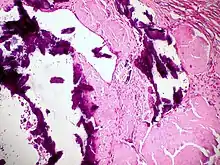

Dystrophic calcification (DC) is the calcification occurring in degenerated or necrotic tissue, as in hyalinized scars, degenerated foci in leiomyomas, and caseous nodules. This occurs as a reaction to tissue damage,[1] including as a consequence of medical device implantation. Dystrophic calcification can occur even if the amount of calcium in the blood is not elevated, in contrast to metastatic calcification, which is a consequence of a systemic mineral imbalance, including hypercalcemia and/or hyperphosphatemia, that leads to calcium deposition in healthy tissues.[2] In dystrophic calcification, basophilic calcium salt deposits aggregate, first in the mitochondria, then progressively throughout the cell. These calcifications are an indication of previous microscopic cell injury, occurring in areas of cell necrosis when activated phosphatases bind calcium ions to phospholipids in the membrane.

- Caseous necrosis in T.B. is most common site of dystrophic calcification.

- Liquefactive necrosis in chronic abscesses may get calcified.